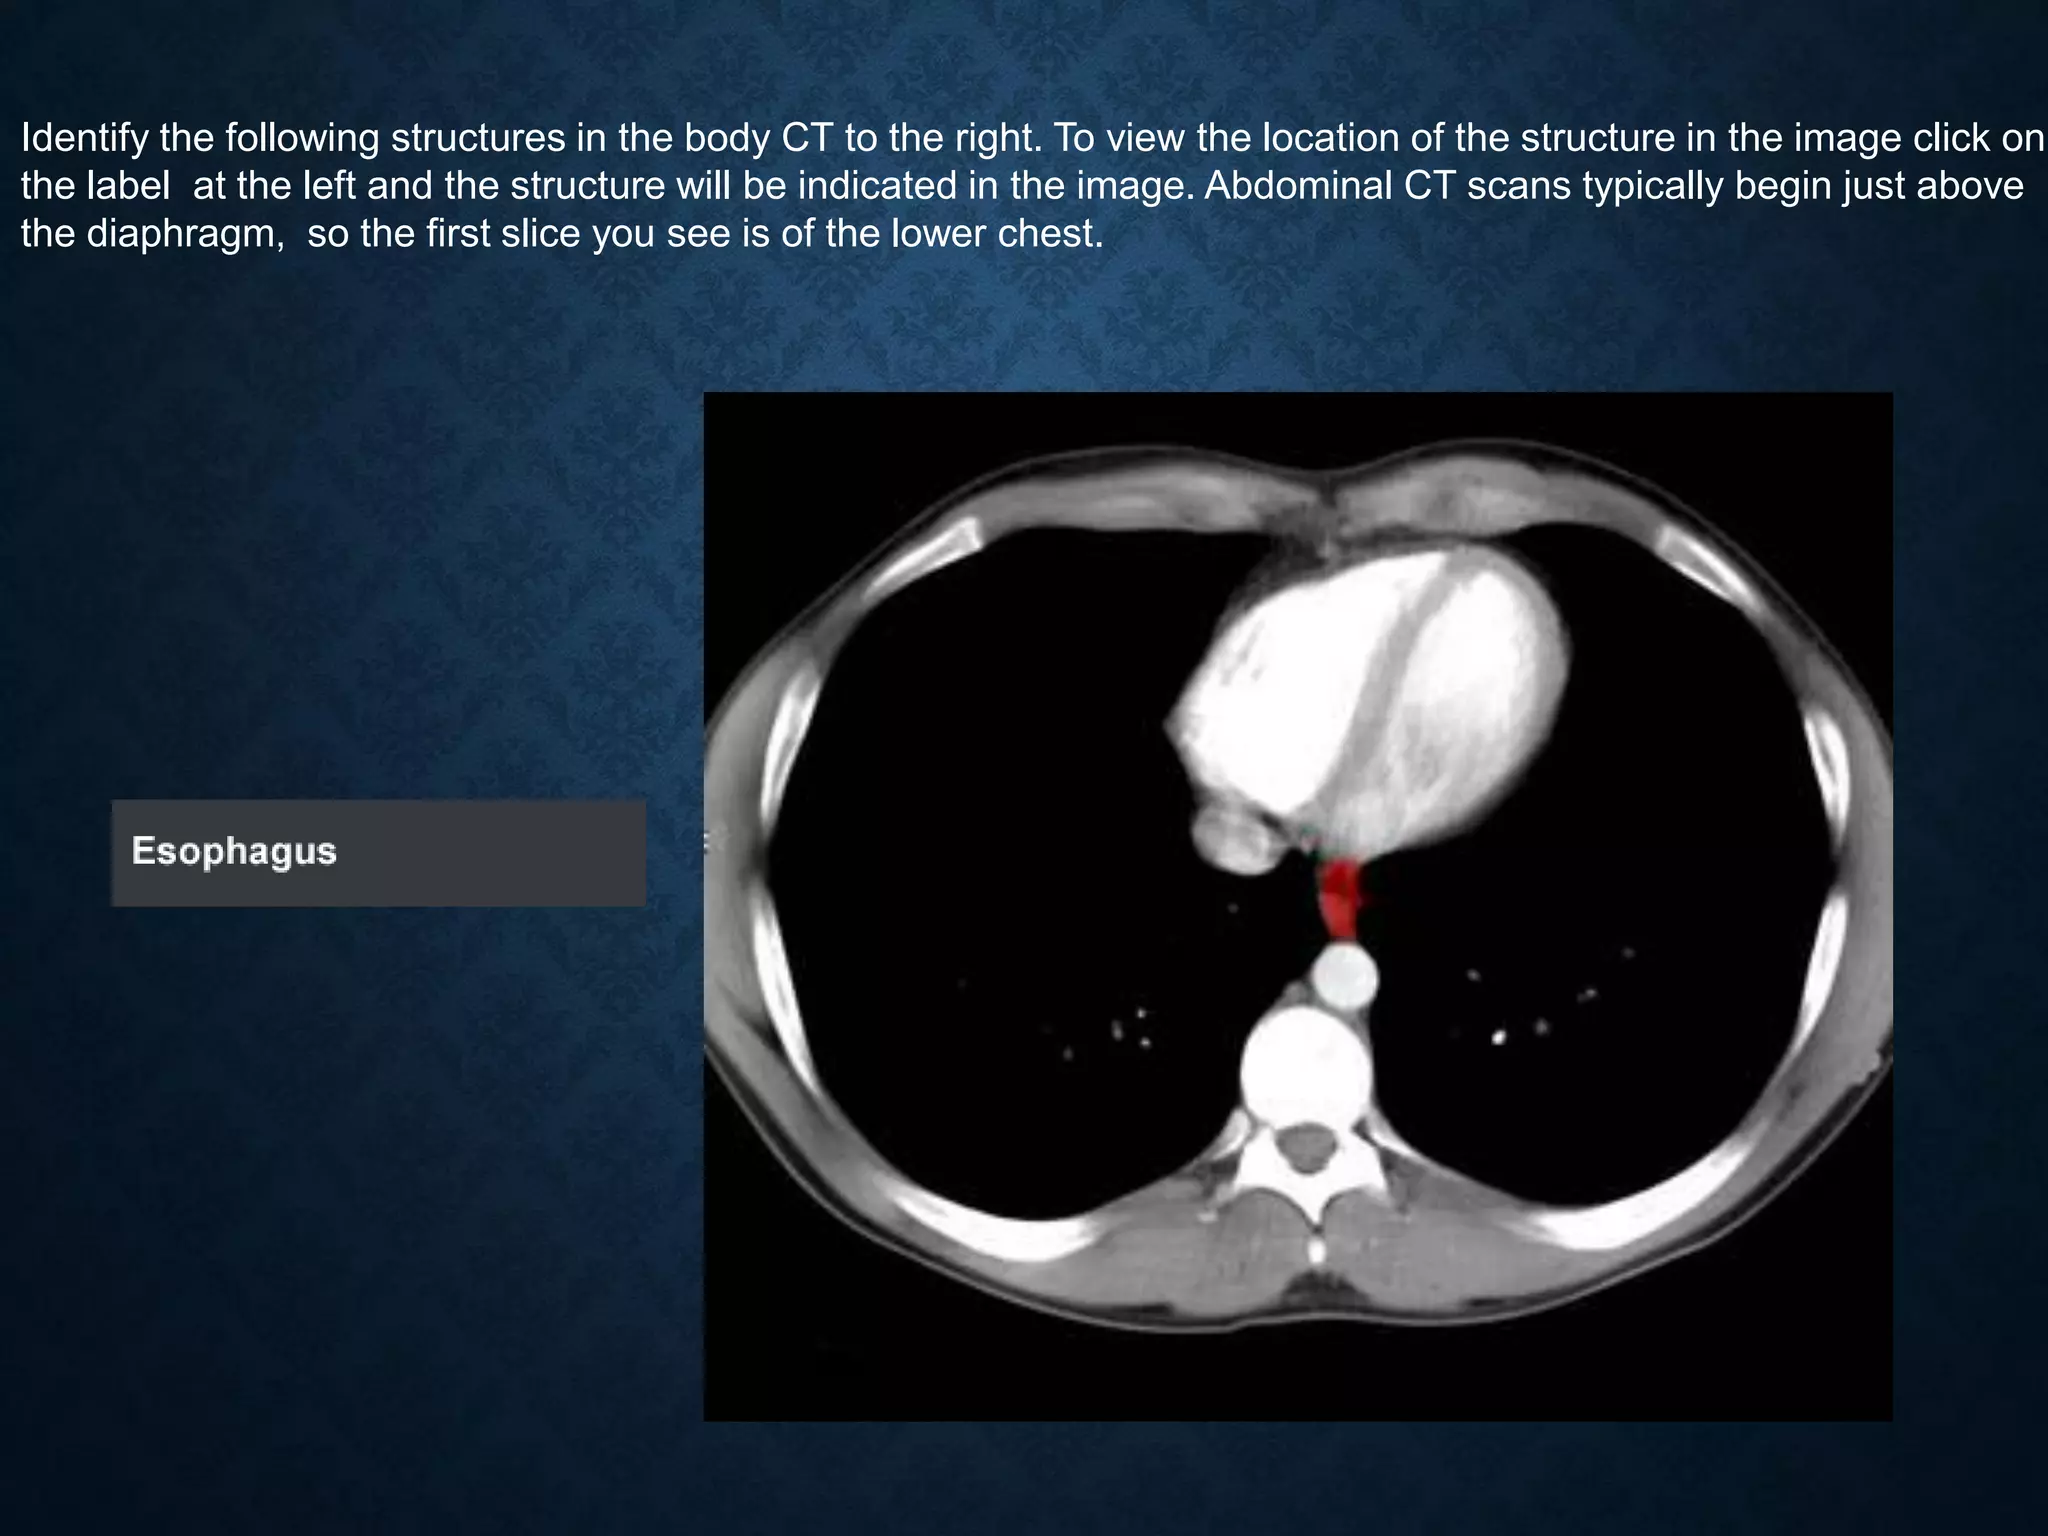

Identify the following structures in the body CT to the right. To view the location of the structure in the image click on

the label at the left and the structure will be indicated in the image. Abdominal CT scans typically begin just above

the diaphragm, so the first slice you see is of the lower chest.

Identify the followingstructures in the body CT to the right. To view the location of the structure in the image click on the label at the left and the structure will be indicated in the image. Abdominal CT scans typically begin just above the diaphragm, so the first slice you see is of the lower chest.